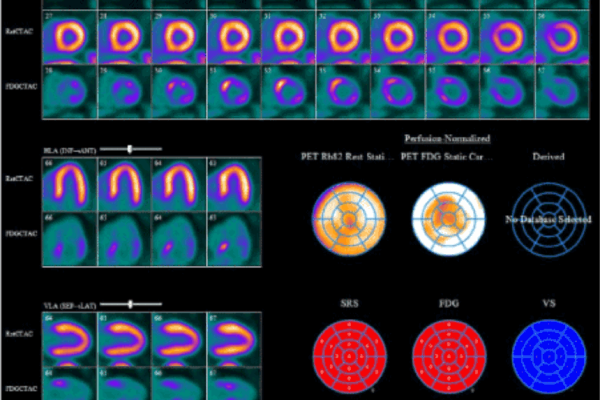

Cardiac PET

Cardiac PET-CT is an advanced imaging technique that evaluates both the blood flow (perfusion) to the heart muscle and the viability of the myocardium (heart tissue). It is particularly useful in identifying areas of the heart that may still benefit from procedures like angioplasty or bypass surgery, even after previous heart damage. Compared to conventional tests such as SPECT or treadmill stress tests, Cardiac PET-CT offers greater accuracy, faster imaging, and lower radiation exposure, making it ideal for high-risk or complex cardiac patients.

Key Indications:

• Assessing myocardial viability in coronary artery disease

• Detection of ischemia in patients with prior heart attacks

• Evaluation before angioplasty or bypass surgery

• Alternative to SPECT when better accuracy is needed